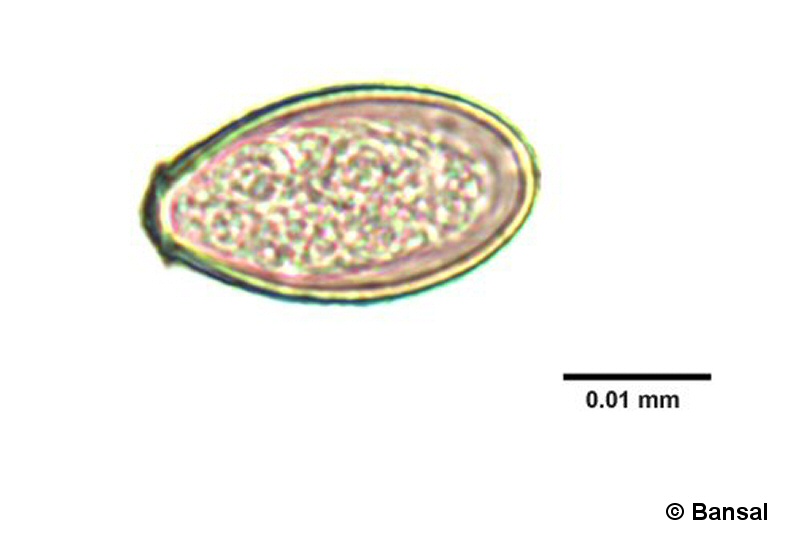

(EN) : Egg: General features, including the small lid-like opening, called operculum, at one end. Possibly an egg from the genus Diphyllobothrium.

(FR) : Œuf : Caractéristiques générales, notamment la petite ouverture en forme de couvercle, appelée opercule, à une extrémité. Il s'agit peut-être d'un œuf du genre Diphyllobothrium.